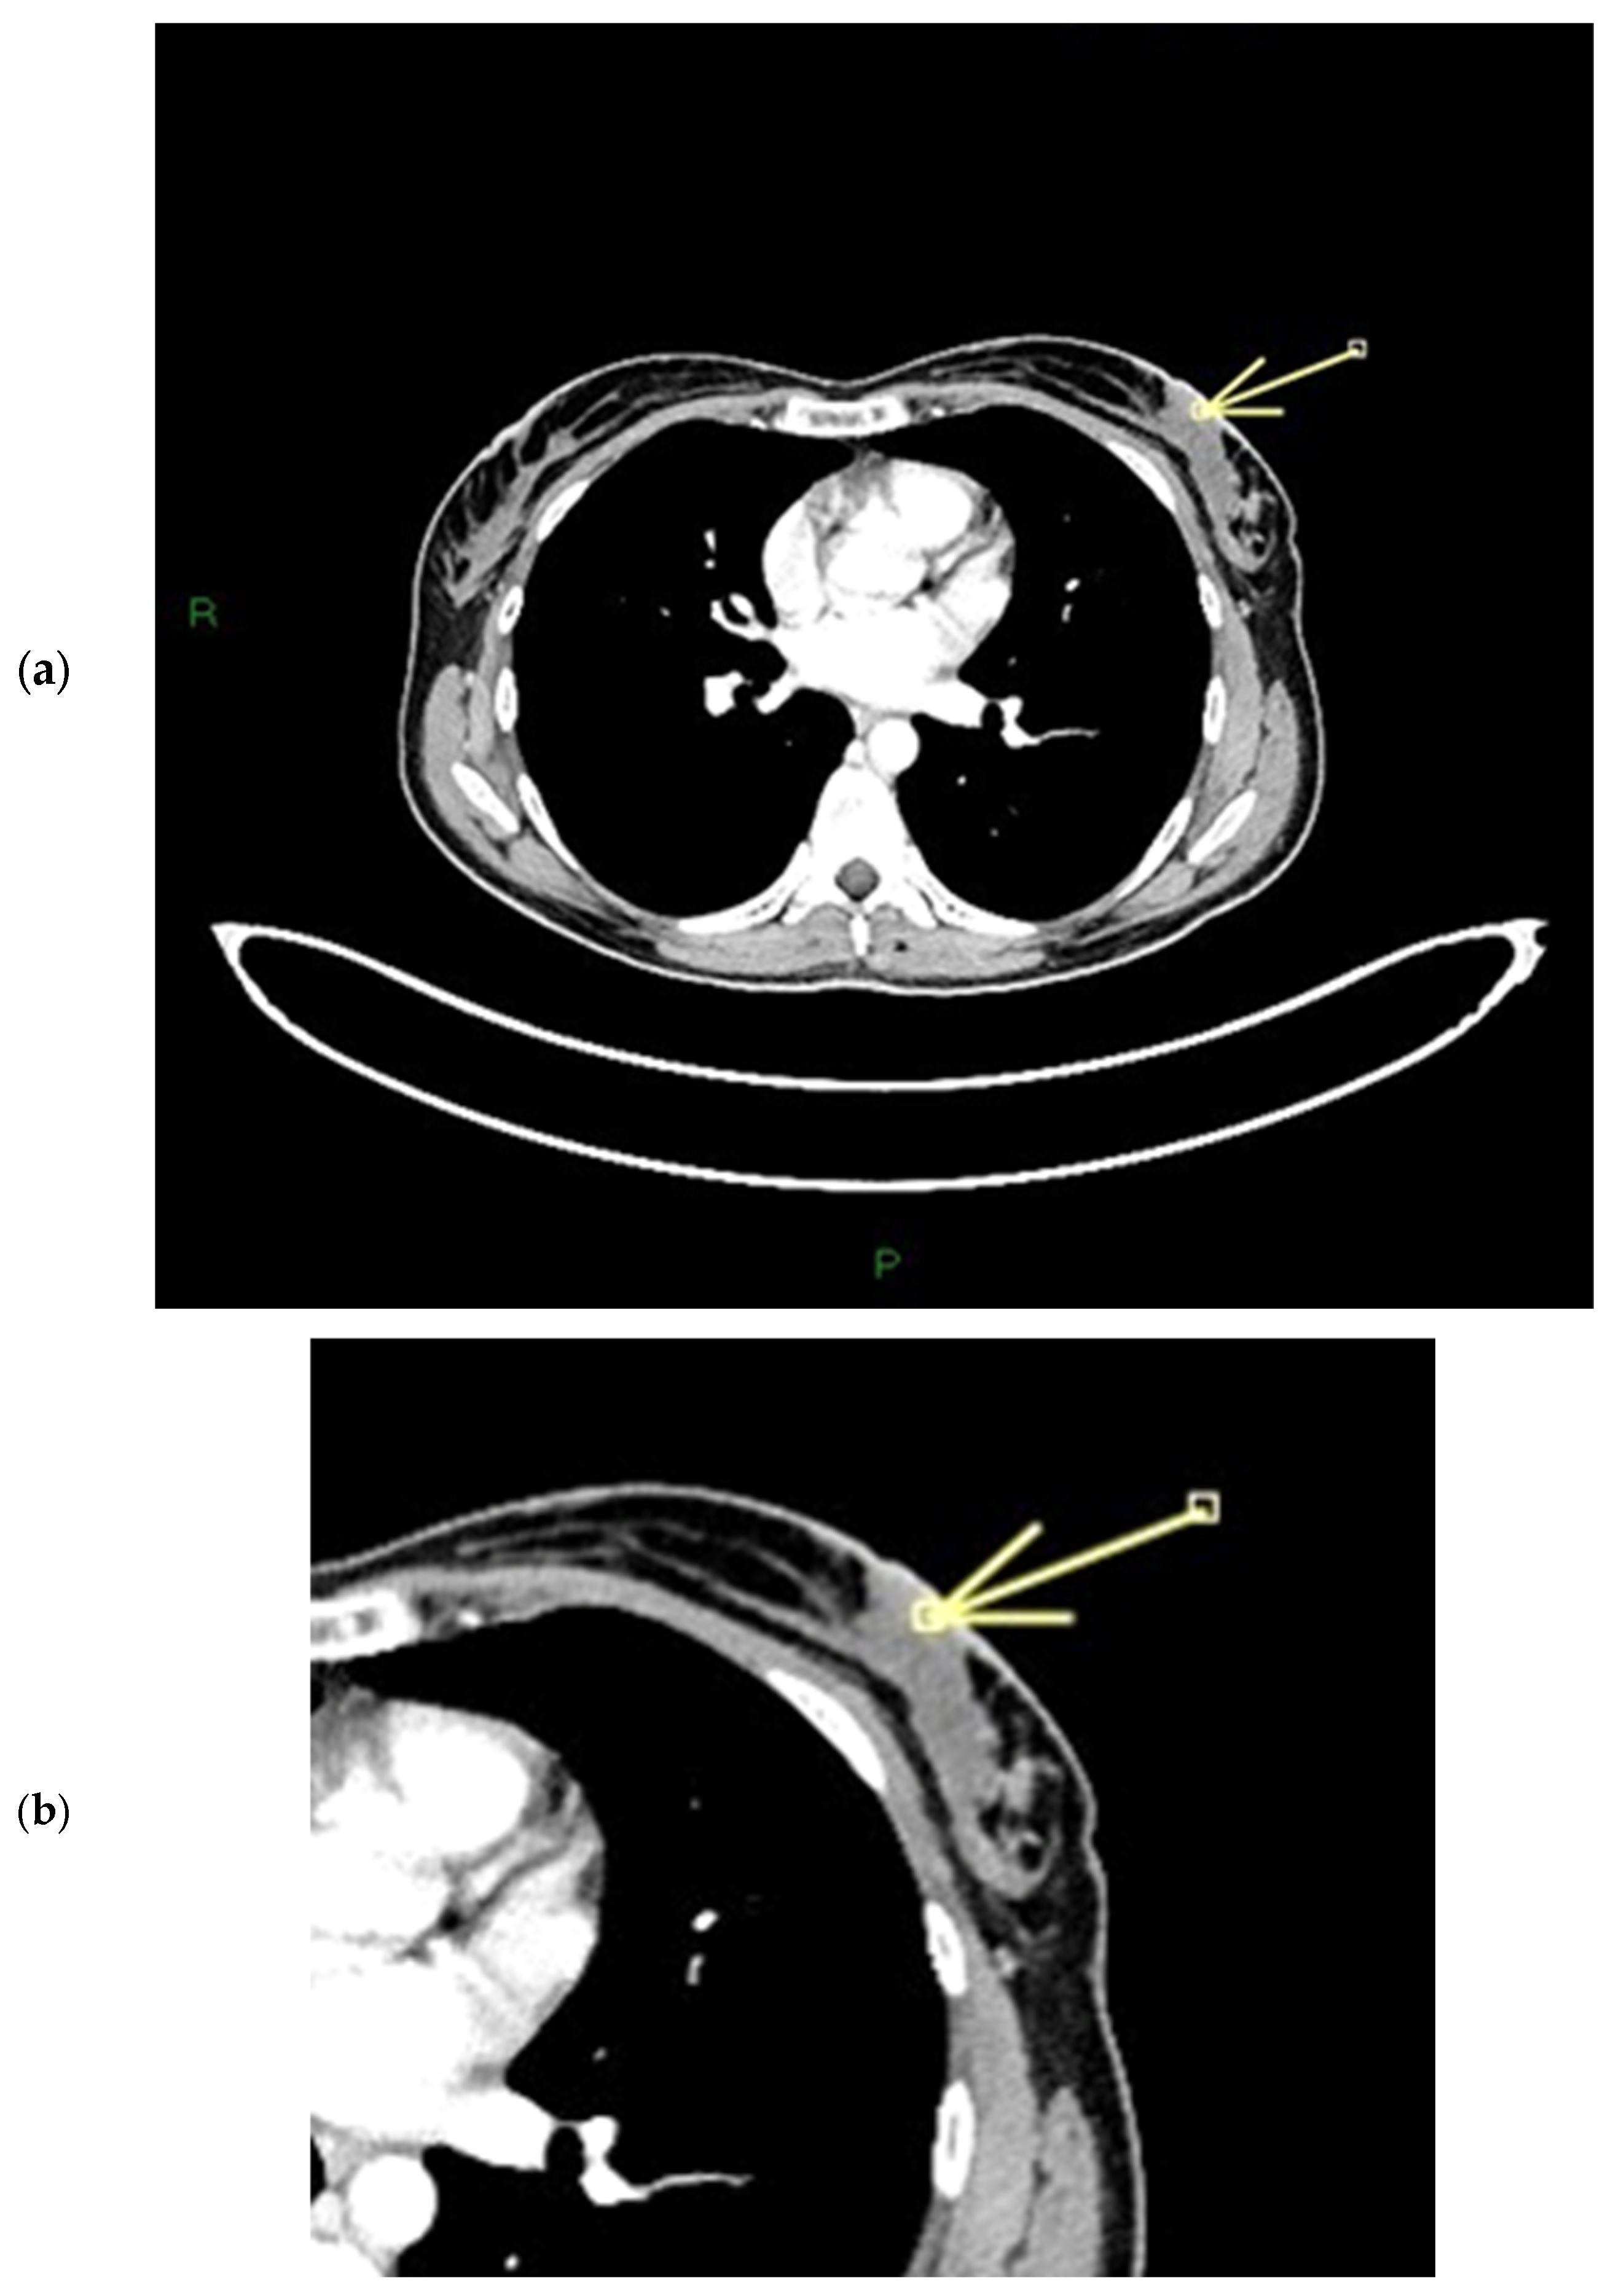

Figure 8.

(a,b) Patient’s name M.E. The ce-CT scan shows enhancement of the base of the left nipple alone (no body; arrow). Morphology of the nipple is everted.